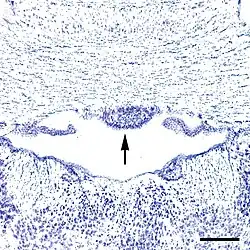

Subfornical organ of a mouse. In this photomicrograph, the subfornical organ (arrow) is located on the undersurface of the fornix in the upper part of the third ventricle. The cells in this coronal section of the brain were colored with a bluish dye ("Nissl stain"). The thalamus is at the bottom of the photo. The bar at the lower right represents a distance of 200 μm (0.2mm).